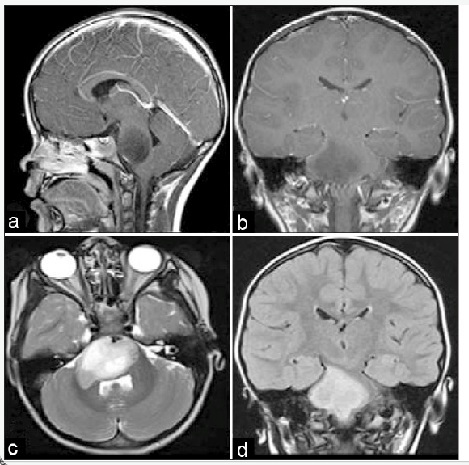

Hasil CT Scan aksial kepala tanpa kontras pada neonatus yang terlihat pada gambar menunjukkan kelainan deformitas yang disebut :

D. Siantosis Metopic

Metopic synostosis also known as Trigonocephaly is caused by premature fusion of the metopic suture. Normally metopic sutures close at 3-9 months of age. Premature fusion can lead to the observed wedge shaped deformity in the cranial vault. There is a resulting restriction of growth in the bilateral frontal bones with compensatory growth in the parietal bones. The deformity can be most easily appreciated above the nasion and extends from the glabella to the anterior fontanelle. Trigonocephaly accounts for approximately 5% of all craniosynostoses and is thought to result from abnormal signaling in growth factors including transforming growth factor (TGF) and fibroblast growth factor (FGF).

Unicoronal synostosis is characterized by flattening of the forehead on the affected side with contralateral bossing which is not present in this CT. This along with the foreshortening of the orbit and zygoma produces the harlequin eye. Sagittal synostosis is also a straightforward diagnosis where the CT shows the characteristic long-boat shaped head along with narrowing of the biparietal diameter. For lambdoid synostosis, the ipsilateral tragus and petrous bone are drawn posteriorly and the midline of the foramen magnum is drawn to the affected side. Bicoronal synostosis is characterized by a very broad and tall forehead from the premature fusion of both sutures with characteristic CT findings. Metopic synostosis and other cranial synostoses may lead to increased intracranial pressure if left untreated as well as other neurocognitive deficits and behavioral abnormalities.